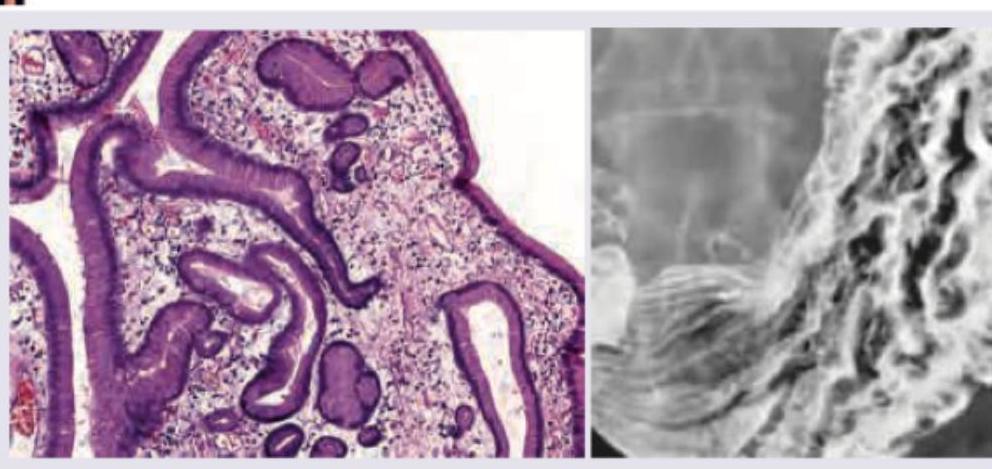

The following histological slide demonstrates:

Explanation: ***Flask-shaped ulcer*** - The image depicts a **flask-shaped ulcer**, which is a characteristic pathological finding in **amoebic dysentery** caused by *Entamoeba histolytica* [1][2]. - These ulcers are formed as the amoebae invade the colonic mucosa, creating a narrow neck at the surface and a wider base in the submucosa [1]. *Pseudopolyps* - **Pseudopolyps** are typically seen in inflammatory bowel diseases like **ulcerative colitis**, resulting from regenerating mucosa surrounded by areas of ulceration [3]. - They are not characteristic of amoebic infections and do not present as deep, flask-shaped lesions. *Blunting of microvilli* - **Blunting of microvilli** is a feature of malabsorptive conditions, such as **celiac disease**, where the villi are damaged. - This finding is related to the absorptive surface of the small intestine and is not a typical macroscopic or microscopic feature of amoebic ulcers in the colon. *Whipple's disease* - **Whipple's disease** is a rare systemic infectious disease caused by the bacterium *Tropheryma whipplei*, primarily affecting the small intestine [4]. - Histologically, it is characterized by **foamy macrophages** in the lamina propria and is not associated with flask-shaped ulcers [4]. **References:** [1] Cross SS. Underwood's Pathology: A Clinical Approach. 6th ed. Common Clinical Problems From Alimentary System Disease, pp. 364-365. [2] Kumar V, Abbas AK, et al.. Robbins and Cotran Pathologic Basis of Disease. 9th ed. The Gastrointestinal Tract, pp. 801-802. [3] Kumar V, Abbas AK, et al.. Robbins and Cotran Pathologic Basis of Disease. 9th ed. The Gastrointestinal Tract, p. 809. [4] Kumar V, Abbas AK, et al.. Robbins and Cotran Pathologic Basis of Disease. 9th ed. The Gastrointestinal Tract, pp. 798-799.